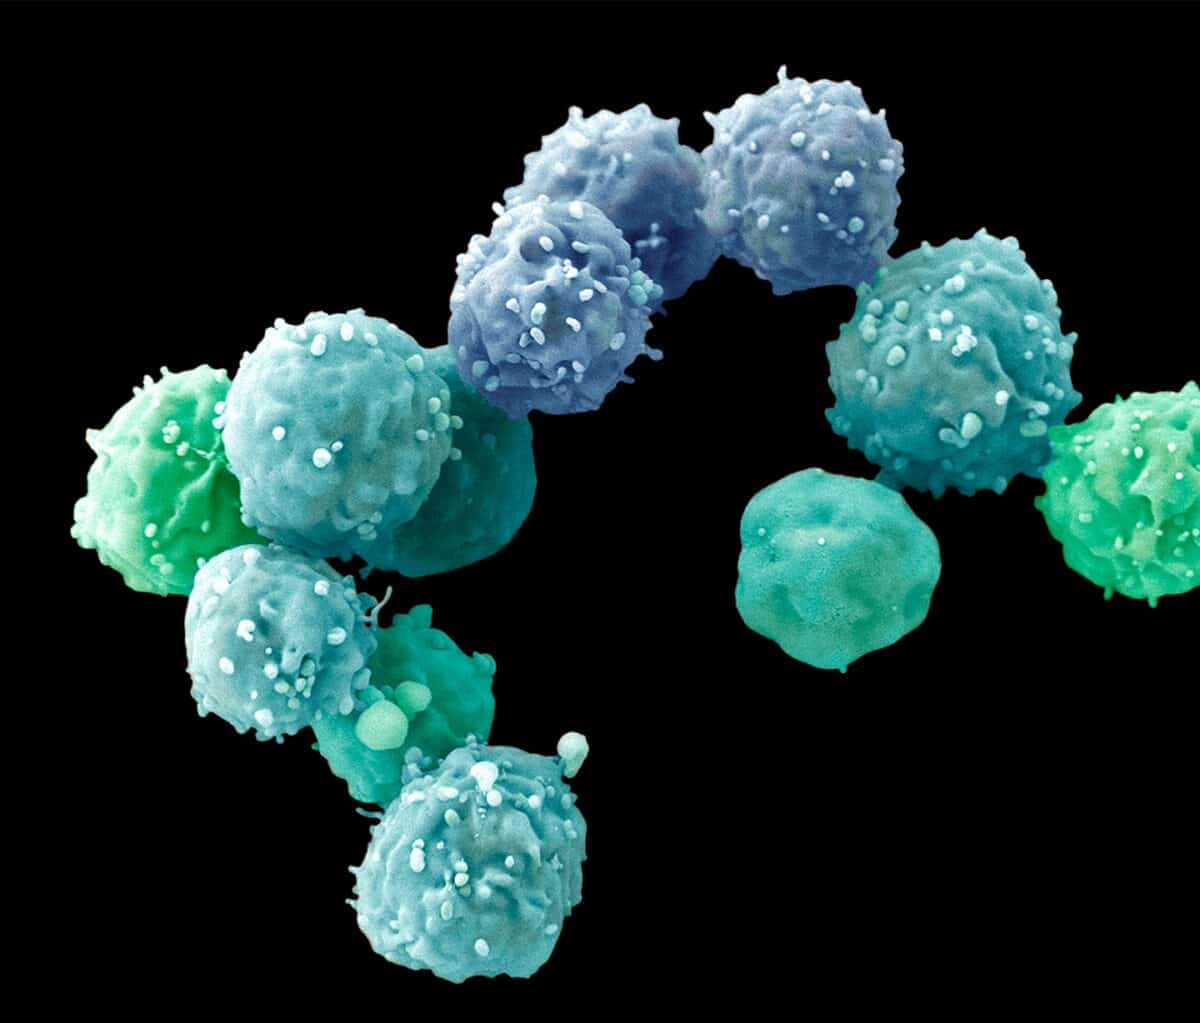

One way around that problem is to work with another kind of 3D cell culture known as a spheroid, which hasn’t yet gone too far down the path of development and still contains mostly identical, similarly differentiated cells.

Much of the work geared toward drug discovery and testing uses spheroids. Lee Rubin, professor of stem cell and regenerative biology at Harvard University, employs them to study spinal muscular atrophy (SMA), a neurodegenerative disease affecting children that is similar to amyotrophic lateral sclerosis (ALS) in adults. “Because I’m interested in developing therapeutics, I need a system that generates billions of human neurons that have the particular mutations for this disease,” he says. Those neurons need to be identical to each other, and to achieve that consistency, Rubin and his colleagues are willing to sacrifice some of the structural complexity they could get with more fully formed organoids. He can control what the spheroids’ cells become—muscle neurons or glial cells, or even muscle or gut cells—by adding particular chemical cues to the medium in which they grow. But because the spheroids were created from a cell carrying the SMA gene, all of the cells, of whatever type, also have that mutation.

Rubin first used spheroids to confirm that, as expected, motor neurons die if they have the disease mutation. “But we also discovered something surprising,” he says. Researchers had assumed that the SMA gene, essential for the survival of motor neurons, affected only that particular type of neuron. But the SMA mutation also generated defects in the other tissue cells—for muscles, gut, lung and thyroid—he derived from the iPS cells they used. That suggested that children with SMA might also suffer other problems affecting muscle tone or digestion, for example, that hadn’t been known or discussed.